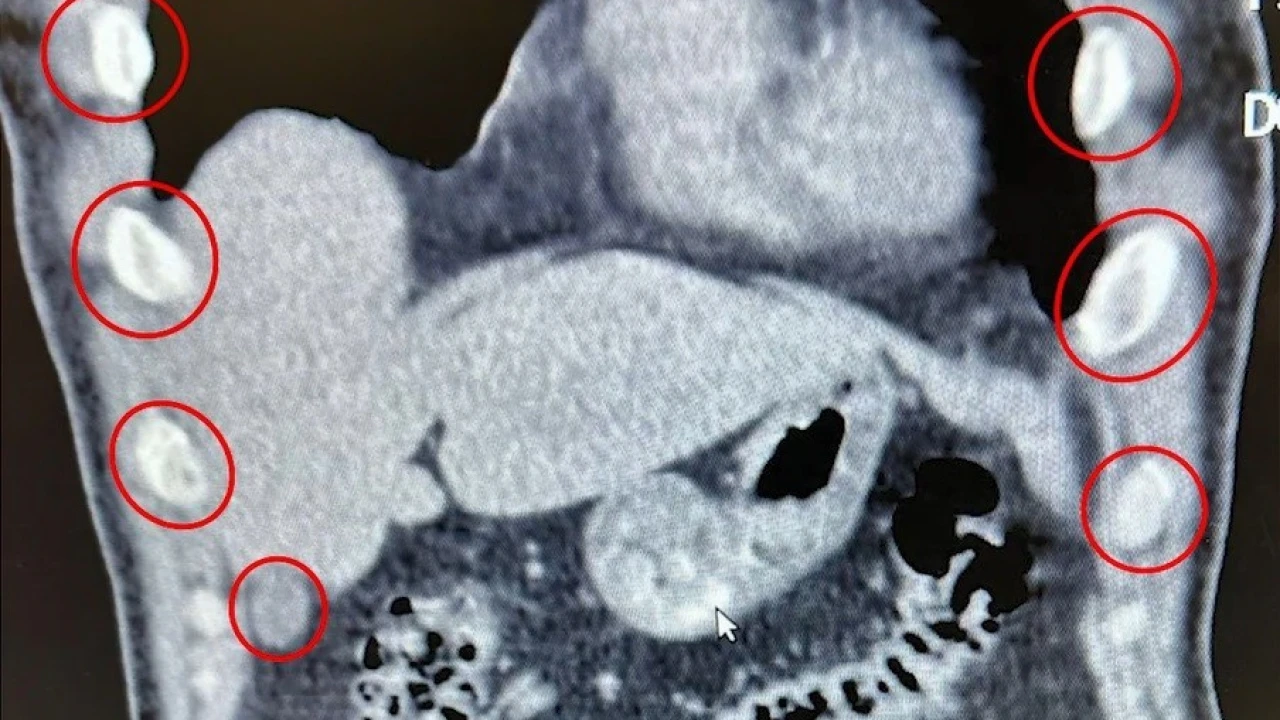

Tatvan ilçesinde durdurulan bir otobüste yolcu olarak seyahat eden yabancı uyruklu 2 kişi gözaltına alındı. Şahısların yapılan tıbbi müdahalesinde, yuttukları 136 kapsül halinde toplam 1 kilo 48 gram metamfetamin ele geçirildi.